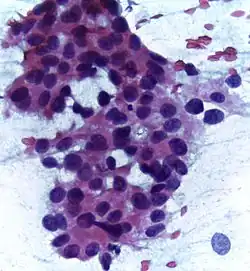

Uma biópsia consiste na recolha de uma pequena quantidade de tecido ou de células da área suspeita que é depois analisada ao microscópio por um patologista. A biópsia é o único exame que permite confirmar um diagnóstico definitivo de cancro. Os restantes exames apenas sugerem a possibilidade do cancro estar presente. A maior parte dos tipos de cancro da mama são facilmente diagnosticáveis por biópsia, embora alguns tipos raros possam necessitar de exames de laboratório especializados. Há vários tipos de biopsias, classificados de acordo com a técnica ou tamanho da agulha usada. Na biópsia de diagnóstico, a técnica geralmente usada é a biópsia por agulha grossa, em que é inserida uma agulha para recolher uma amostra de tecido da massa suspeita. Pode também ser usada a técnica de biópsia por agulha fina, em que o diâmetro da agulha é menor e é recolhida apenas uma amostra de células ou de líquido. A presença de líquido transparente geralmente indica que o nódulo não é cancerígeno. Por outro lado, se o líquido contiver sangue, pode ser analisado ao microscópio para detetar a presença de células cancerígenas.[77][79]

A análise laboratorial da amostra recolhida pela biópsia permite conhecer as características do cancro e ajuda a definir a melhor opção de tratamento. Entre as características, a análise determina se o tumor é invasivo ou in situ, ductal ou lobular e se o cancro se espalhou para os gânglios linfáticos ou não. A análise permite também avaliar se o cancro é positivo ao receptores hormonais (ER+ e PR+), de modo a determinar o risco de recorrência da doença e qual o tratamento com melhor probabilidade de diminuir esse risco, e se é positivo ao gene do receptor-2 do factor de crescimento epidérmico humano (HER2+), o que permite saber se o tratamento com anticorpos é eficaz. É também a partir da biópsia que se determina o grau do tumor; ou seja, quão diferentes são as células cencerosas das células normais e se elas aparentam crescer lentamente ou rapidamente.[77]

O cancro da mama pode ser classificado de acordo com a sua aparência histológica. A maior parte dos tumores malignos da mama tem origem em carcinomas no tecido epitelial. Os carcinomas da mama, embora muitas vezes discutidos na qualidade de uma única doença, são na realidade um grupo diversificado de lesões que diferem entre si na aparência ao microscópio e no comportamento biológico. A sua classificação depende das características citológicas das lesões, do tipo de recetores que as células apresentam e da sua velocidade de proliferação, e não da localização no sistema ductal-lobular mamário.[82] Quando o crescimento das células pré-malignas é restrito a um determinado compartimento, sem invadir o tecido envolvente, denomina-se "carcinoma in situ". Pelo contrário, quando o carcinoma não se restringe ao compartimento inicial denomina-se "carcinoma invasivo".[83]